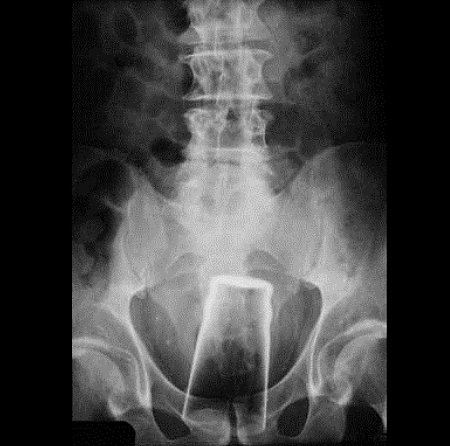

Malum Bölgelerine Kazayla Giren Nesneler Sonucu Acile Kaldırılmış İnsanların 15 Röntgen Görüntüsü  Bu nesnelerin orada olmasının mantıklı hiçbir alakası yok. Büyük ihtimalle bir kaza sonucu bu durum oluşmuştur. Aksini düşünmek bile istemiyorum. Foto Galerimizin devamını görmek için Lütfen sonraki sayfaya geçiniz..